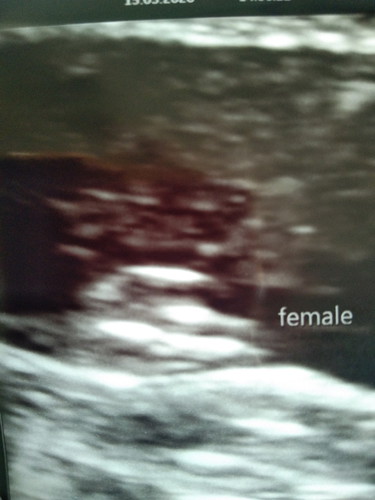

ตอนนี้ท้องได้ 21 วีคแล้วไปอัลตร้าซาวด์มาหมอบอกว่าเป็นลูกสาวมีโอกาสไหมที่หมอจะอัลตร้าซาวด์ผิดเพศเพราะอยากได้ลูกชายมากรู้สึกผิดหวังแล้วก็เครียดมาก

โอกาสน้อยค่ะ เพราะอายุครรภ์ 4 เดือน+ แล้ว จะเพศไหนน้องก็มาอยู่กับเราแล้วนะคะ ดูแลน้องดีๆค่ะ ☺️